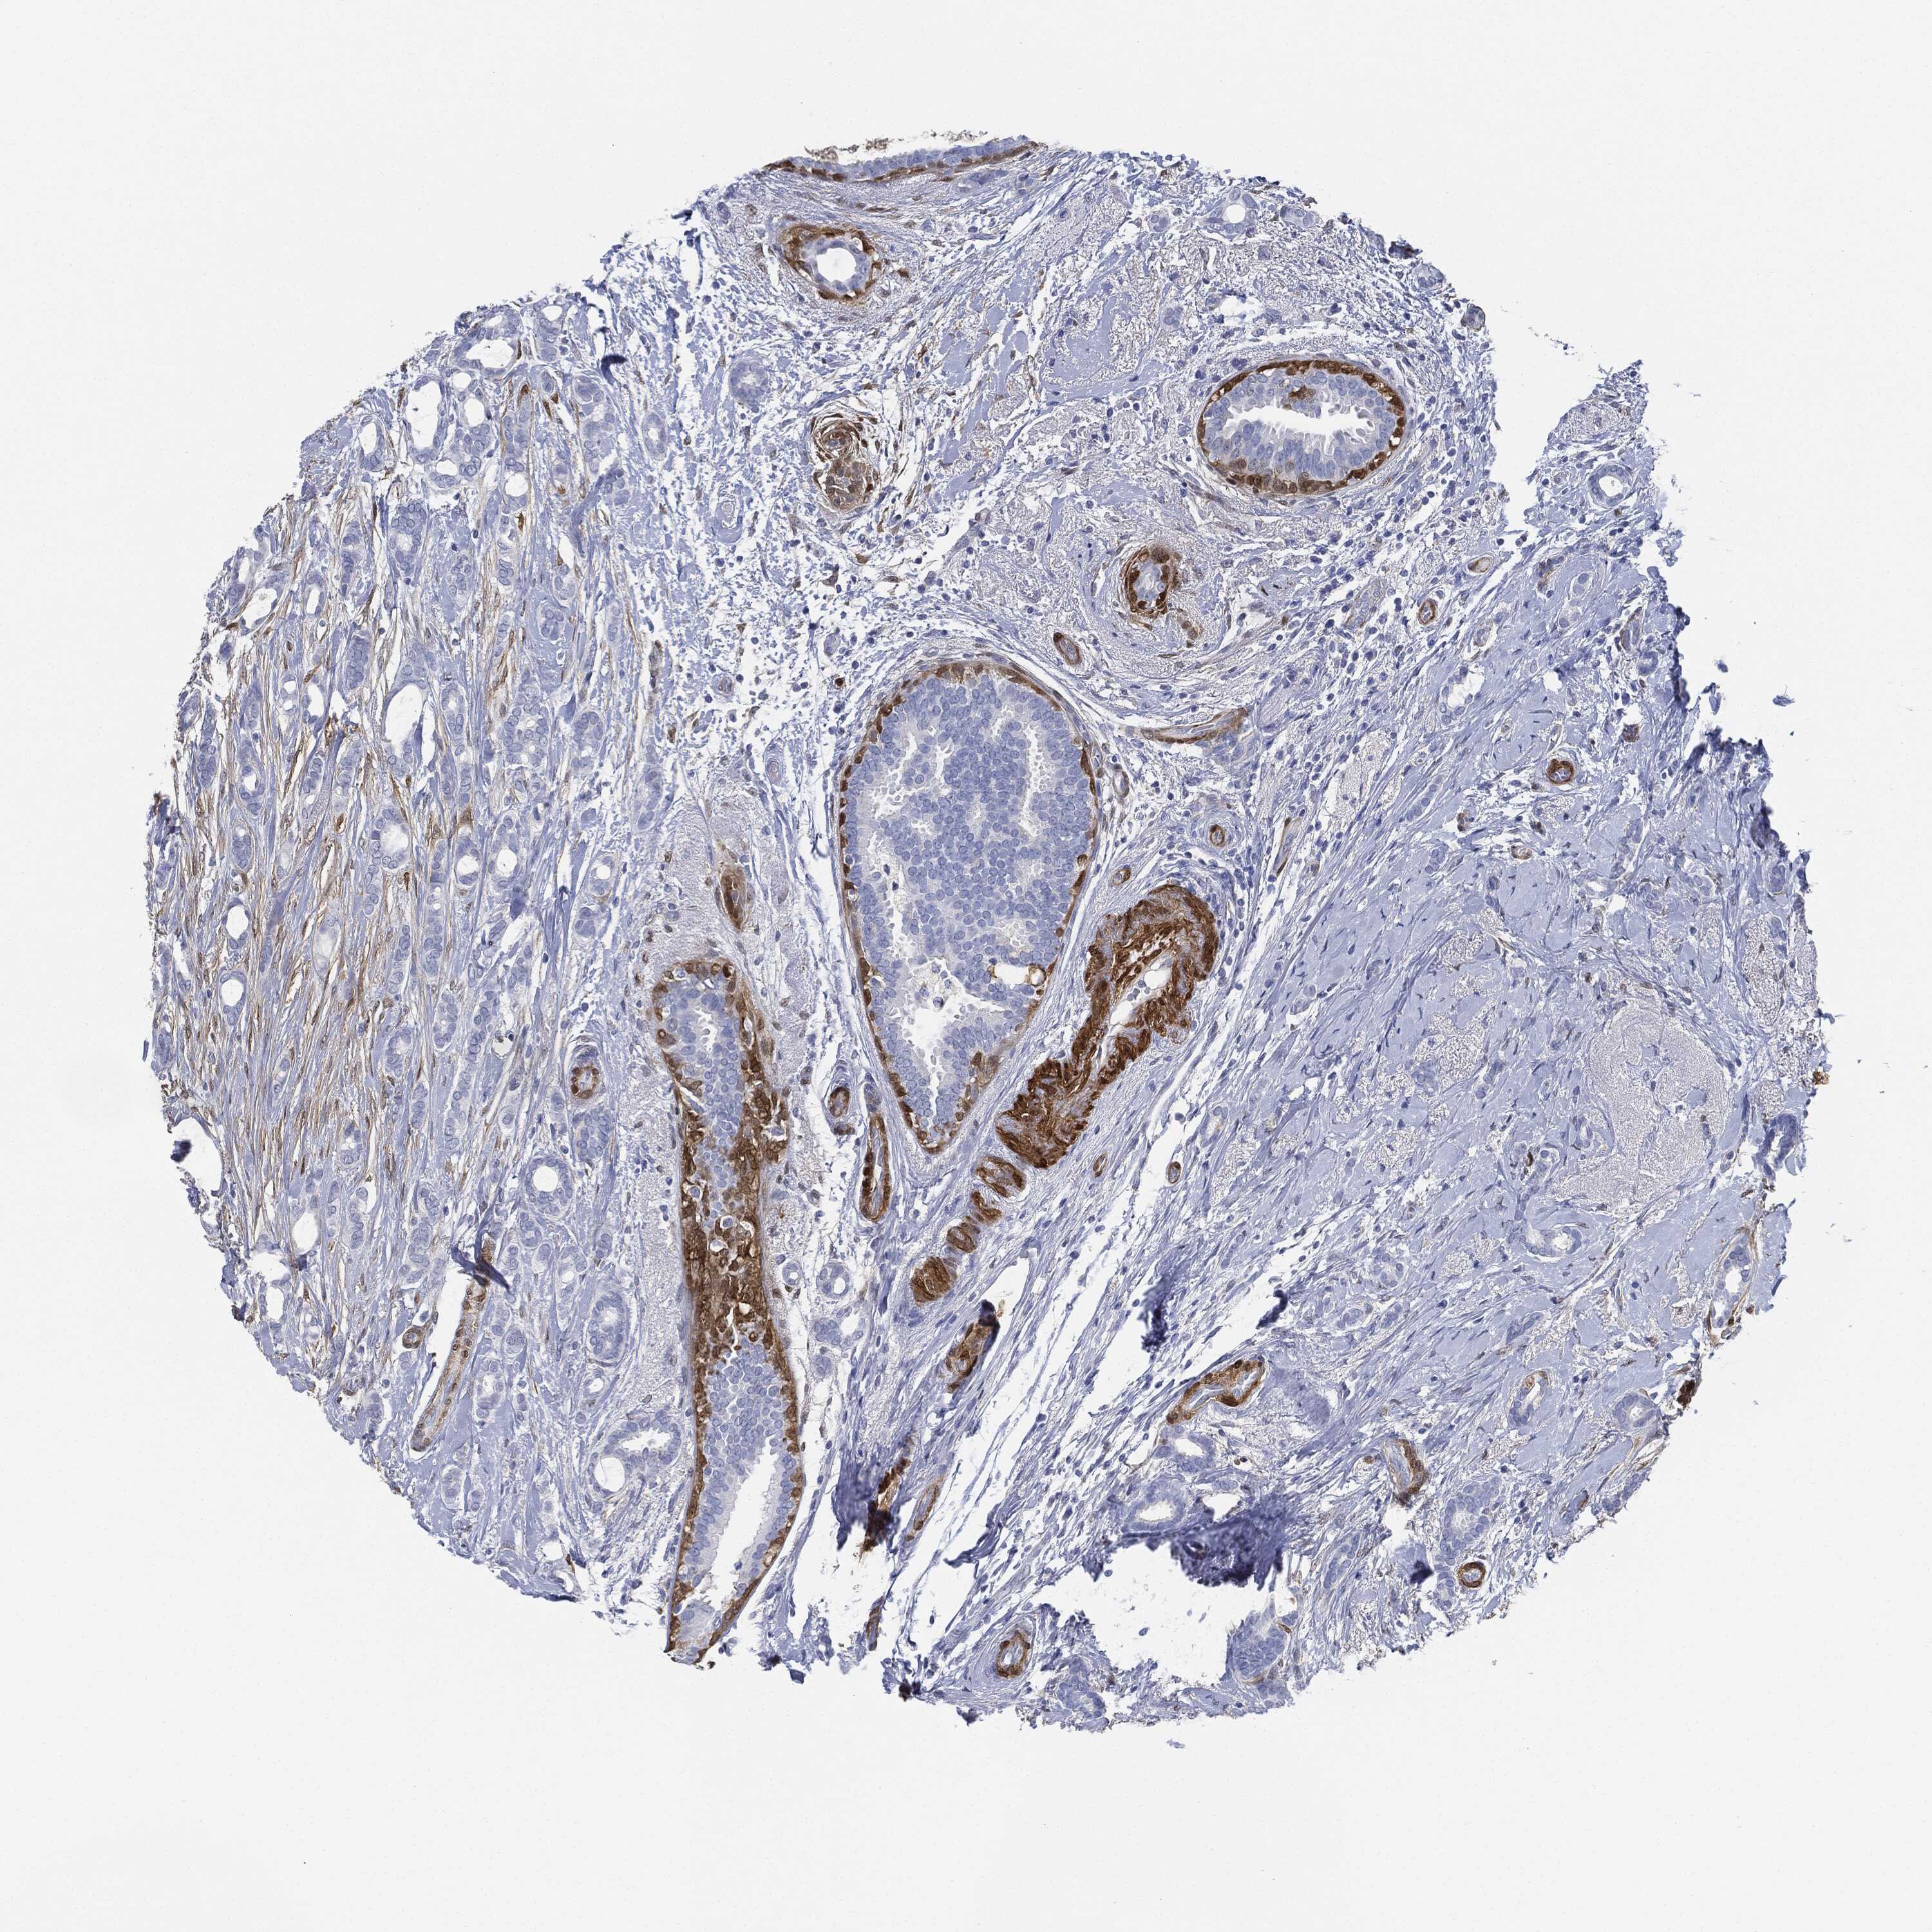

BRCA TCGA BRCA VALIDATION PROTEIN EXPRESSION

ANTIBODIES

AND

VALIDATION